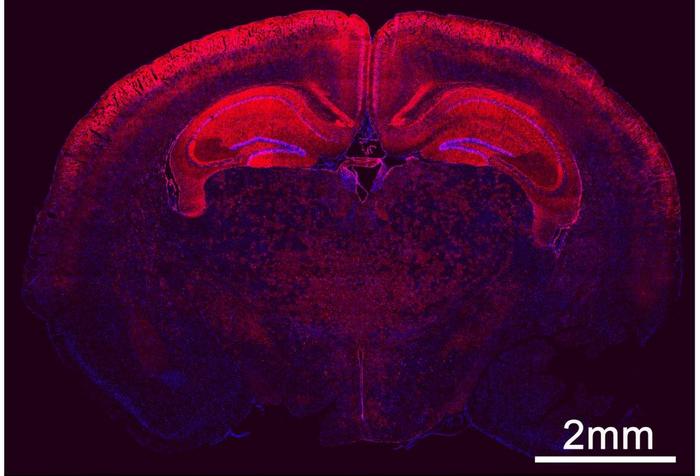

The researchers injected the LNP with the mRNA into the fetal brain's ventricles in a mouse model. The mRNA translates into CAS9, a protein that works like scissors for gene editing. The produced CAS9 will edit the gene responsible for Angelman syndrome.

Using tracers, the researchers could see all the neurons that were edited inside the brain. Their study showed that the nanoparticles were taken up by the brain’s developing neural stem and progenitor cells. The nanoparticles led to gene edits in 30% of the brain stem cells in the mouse model.

In the study, as the fetal development continued, the stem cells proliferated and migrated to form the central nervous system. The study revealed that more than 60% of the neurons in the hippocampus and 40% of neurons in the cortex were transfected.